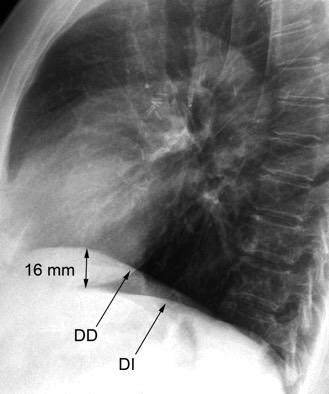

38 .BOTÓN AÓRTICO. DOBLE CONTORNO DEL